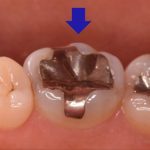

メタルフリー治療。ジルコニアクラウンを奥歯に作製

治療前 治療後 年齢・性別 50代女性 相談内容 奥歯に古い銀の詰め物が入ってい ...